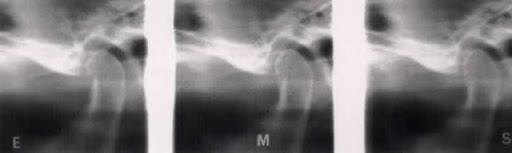

Transcranianas

Se a ATM for radiografada em projeção direta lateral, ou seja, paciente com plano sagital mediano paralelo ao plano do filme e raio X perpendicular a ambos, o feixe central não estará passando na direção do longo eixo do côndilo, e portanto, não estará projetando a melhor imagem daquela estrutura. Então, para que se consiga a projeção mais adequada dos côndilos da mandíbula, será necessário que o ponto de entrada dos raios X seja acima das estruturas altamente radiopacas dos rochedos e na direção do longo eixo do côndilo (7cm acima e 7cm atrás da articulação do lado oposto) (1).

O que se vê realmente da ATM são as estruturas intrinsecamente relacionadas com esta articulação, como: forame auditivo externo, o côndilo, a cavidade glenóide e o tubérculo articular do temporal. Todas as estruturas visíveis por esta projeção cabem num diâmetro de 7 cm, isto permite que efetue-se três exposições em metade do filme de18x24cm (uma em repouso, outra em abertura normal e a terceira em abertura máxima) e outras três na outra metade, para a ATM do outro lado.(1)

Este é o exame mais solicitado para avaliação das imagens da ATM quando se suspeita de desordem intra-articular, ou para verificar a capacidade de translação condilar. Possui custo relativo, porém tem como desvantagens a sobre posição das porções condilares (central e medial) a outras estruturas.(15)